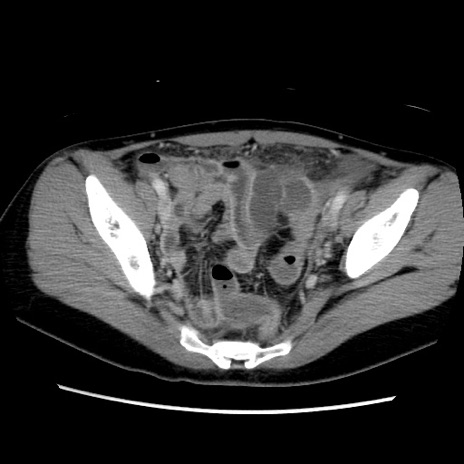

症例39(横断像)

【症例】40歳代女性

【主訴】上下腹部痛

【現病歴】2日目から下腹部痛あり。夜間は痛みで眠れなかった。昨日より上腹部痛と下痢が出現。臥位で痛みは軽快したため、休んでいた。本日になって臥位でも立位でも痛みが強くなってきたため救急要請。

【既往歴】子宮内膜症

【身体所見】部:平坦・軟、左上下腹部に圧痛あり、反跳痛あり。

【データ】WBC 21800、CRP 26.78